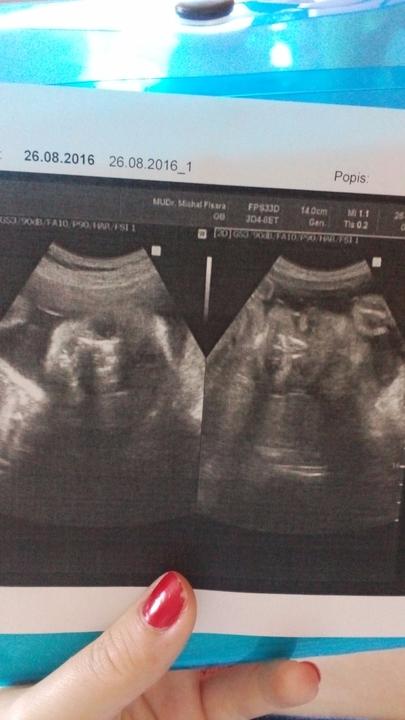

Včerejší kontrola opět dopadla dobře oba hlavičkami dolů, a mají po 450 g 🙂 šikuláci